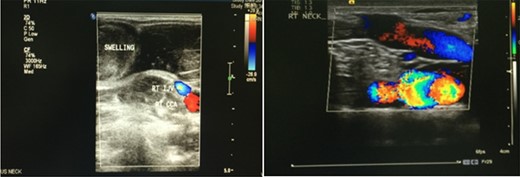

A Doppler ultrasound showed a well-defined, compressible, cystic lesion measuring 4.2 × 1.9 cm, causing an indentation of the right sternocleidomastoid muscle. It contained a venous pattern of flow with communication between itself and the internal jugular vein (Fig. 1).

A Doppler ultrasound showing a well-defined, compressible, cystic lesion measuring 4.2 × 1.9 cm, causing an indentation of the right sternocleidomastoid muscle. The mass contained a venous pattern of flow with communication between itself and the internal jugular vein.